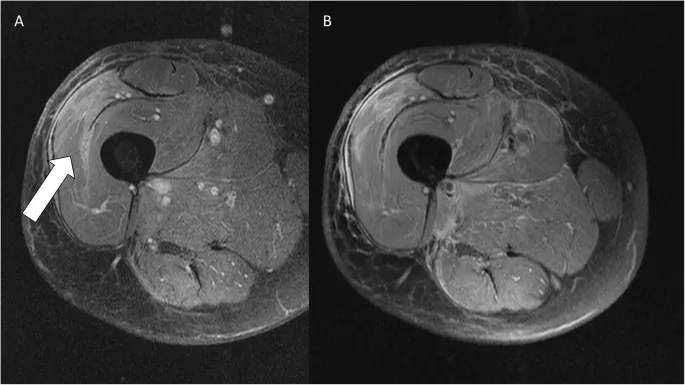

⭐ MRI is the imaging modality of choice for local staging and characterization of soft tissue tumors, detailing extent and neurovascular relations.

- X-ray (calcification, bone changes), CT chest (metastases), PET-CT (high-grade, staging, response).